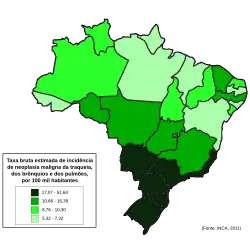

Epidemiologia

|

não há dados

≤ 5

5-10

10-15

15-20

20-25

25-30

|

30-35

35-40

40-45

45-50

50-55

≥ 55

|

Em todo o mundo, o câncer de pulmão é o câncer mais comum em termos de incidência e mortalidade. Em 2008, houve 1,61 mihão de novos casos e 1,38 milhão de mortes por câncer de pulmão. As maiores taxas estão na Europa e na América do Norte.[116] O segmento populacional mais propenso a desenvolver câncer de pulmão está acima dos 50 anos de idade e apresenta histórico de tabagismo. Em contraste com a taxa de mortalidade nos homens, que começou a declinar há 20 anos, a mortalidade do câncer de pulmão nas mulheres tem sido ascendente ao longo das últimas décadas e, apenas recentemente, tem começado a se estabilizar.[117] Nos EUA, o risco de desenvolver câncer de pulmão ao longo da vida é de 8% em homens e de 6% em mulheres.[7]